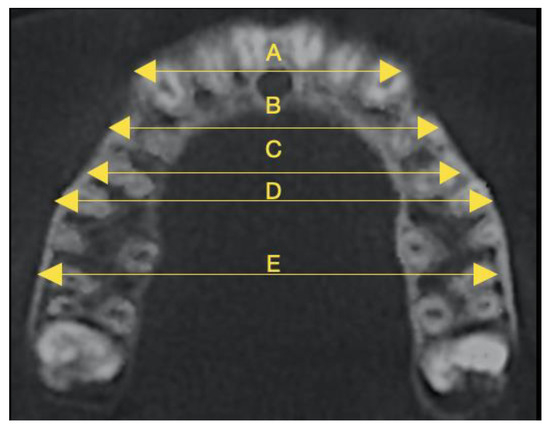

2. Materials and Methods

| Alveolar bone | 0.09 ± 0.22 | 0–1.20 | 0.14 ± 0.39 | 0–2.04 | 0.009 * |

| Buccal alveolar ridge | 1.01 ± 0.38 | 0.30–2.80 | 1.80 ± 0.69 | 0.53 ± 5.03 | 2.83857 × 10−24 ** |

| Palatal alveolar ridge | 0.81 ± 0.37 | 0–1.30 | 2.24 ± 1.04 | 0–4.05 | 2.08145 × 10−20 ** |

| Inter-Apex Width | T1-T0 (mm) (Mean ± SD) | T1-T0 Minimum–Maximum Values (mm) | T1-T0 (%) (Mean ± SD) | T1-T0 Minimum–Maximum Values (%) | p-Value |

|---|---|---|---|---|---|

| Intercanine | 1.31 ± 0.73 | 0.10–2.50 | 4.39 ± 2.43 | 0.34–8.39 | 5.84596 × 10−17 ** |

| First interpremolar | 1.89 ± 0.39 | 0.7–2.6 | 5.18 ± 1.11 | 1.93–7.22 | 1.07006 × 10−35 ** |

| Second interpremolar | 1.48 ± 0.68 | 0.10–2.60 | 3.53 ± 1.63 | 0.24–6.15 | 2.33339 × 10−20 ** |

| First intermolar | 0.70 ± 0.26 | 0.10–1.20 | 1.40 ± 0.53 | 0.20–2.41 | 4.20634 × 10−24 ** |

| Second intermolar | 0.15 ± 0.09 | 0–0.40 | 0.29 ± 0.17 | 0–0.77 | 2.28014 × 10−16 ** |

| Inter-Cusp Width | T1-T0 (mm) (Mean ± SD) | T1-T0 Minimum–Maximum Values (mm) | T1-T0 (%) (Mean ± SD) | T1-T0 Minimum–Maximum Values (%) | p-Value |

| Intercanine | 2.32 ± 0.33 | 1.40–3.60 | 7.37 ± 1.11 | 4.18–11.76 | 2.39215 × 10−43 ** |

| First interpremolar | 3.44 ± 0.22 | 3.10–3.90 | 8.65 ± 0.60 | 7.71–10.13 | 1.1346 × 10−60 ** |

| Second interpremolar | 3.14 ± 0.27 | 2.70–3.60 | 6.94 ± 0.65 | 5.71–8.13 | 5.72304 × 10−54 ** |

| First intermolar | 2.60 ± 0.52 | 0.40–3.40 | 5.74 ± 1.19 | 0.90–7.64 | 1.4256 × 10−35 ** |

| Second intermolar | 0.70 ± 0.28 | 0.10–1.80 | 1.24 ± 0.51 | 0.18–3.24 | 1.2904 × 10−22 ** |